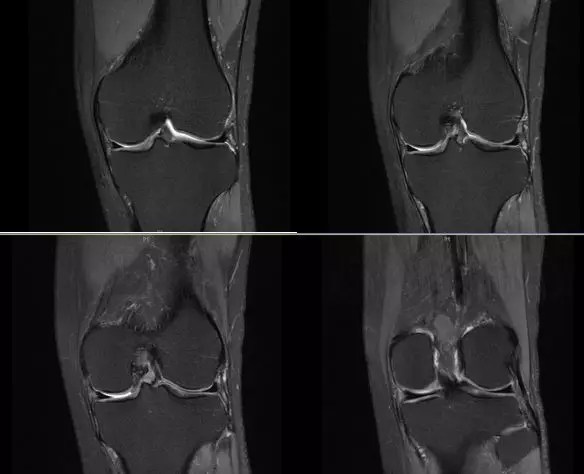

膝关节内侧副韧带

膝关节后外侧结构

内侧支持带撕裂